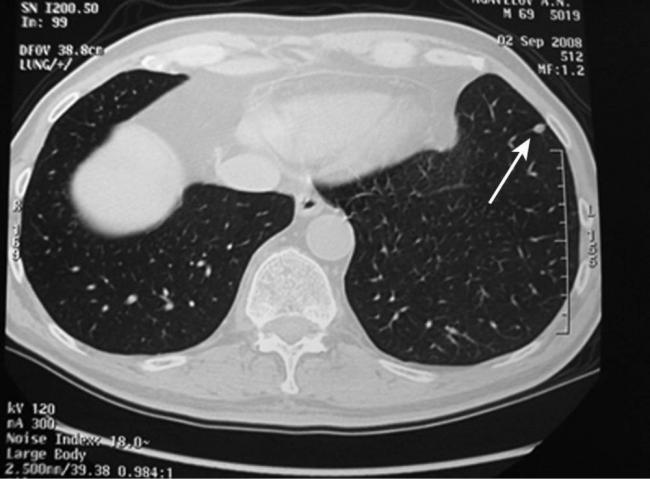

Чтобы человек несведущий смог разобраться в результатах КТ, следует знать о нюансах чтения снимков. Рассмотрим самые актуальные:

- Очаговые образования представляют собой участки белого цвета на черном фоне (на снимке-негативе). В реальности пораженная область, скорее всего, имеет более темный цвет, чем здоровые ткани легкого.

- Если врач заметит на снимке участки кальцинирования или обызвествления (капсул, пропитанных солями кальция) вокруг очага, это может быть признаком доброкачественности образования. Кальцинаты по цвету похожи на кости скелета, видимые на этом снимке. Такие явления часто обнаруживаются после затяжных простудных заболеваний, бронхитов или уже излечененного туберкулеза и представляют собой некий шрам на легких. Пациента с образованием, на котором заметны признаки кальцината, пульмонологи обычно просят раз в полгода делать контрольные снимки.

- В случае, когда образование представляет собой так называемое «облачко» или очаг по типу «матового стекла», требуется более предметное обследование. Внешне оно выглядит как затуманенная область с размытыми границами. В ряде стран пациентам с такими образованиями сразу рекомендуется операция, даже если оно не растет. Уже доказано, что в 80% случаев такие очаги являются предраковым состоянием легких. Альтернатива немедленной операции — постоянное наблюдение с контрольными снимками раз в полгода-год.